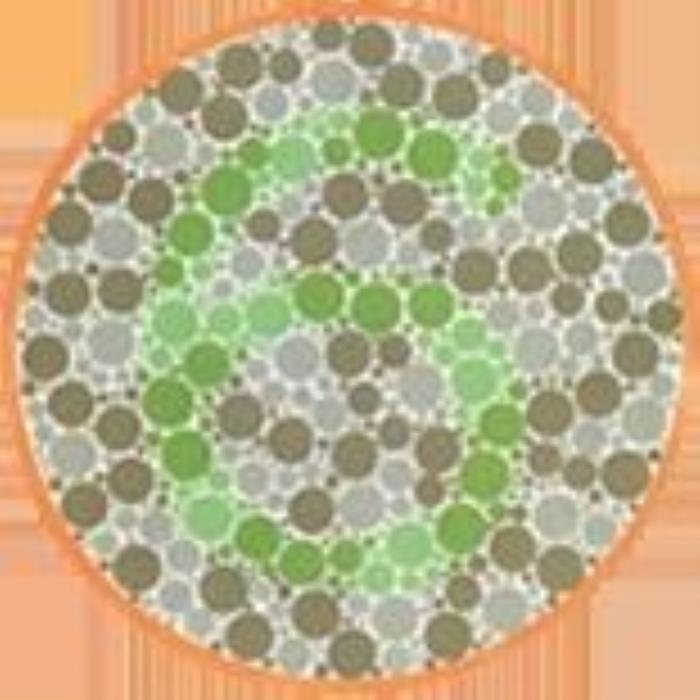

·形状图1

结果:正常看到的是正方形、三角形

·形状图2

结果:正常看到的是一大一小,两个圆形

·形状图3

结果:正常看到的是一个圆形

·形状图4

结果:正常看到的是五角星(可以尝试离手机远一点看)